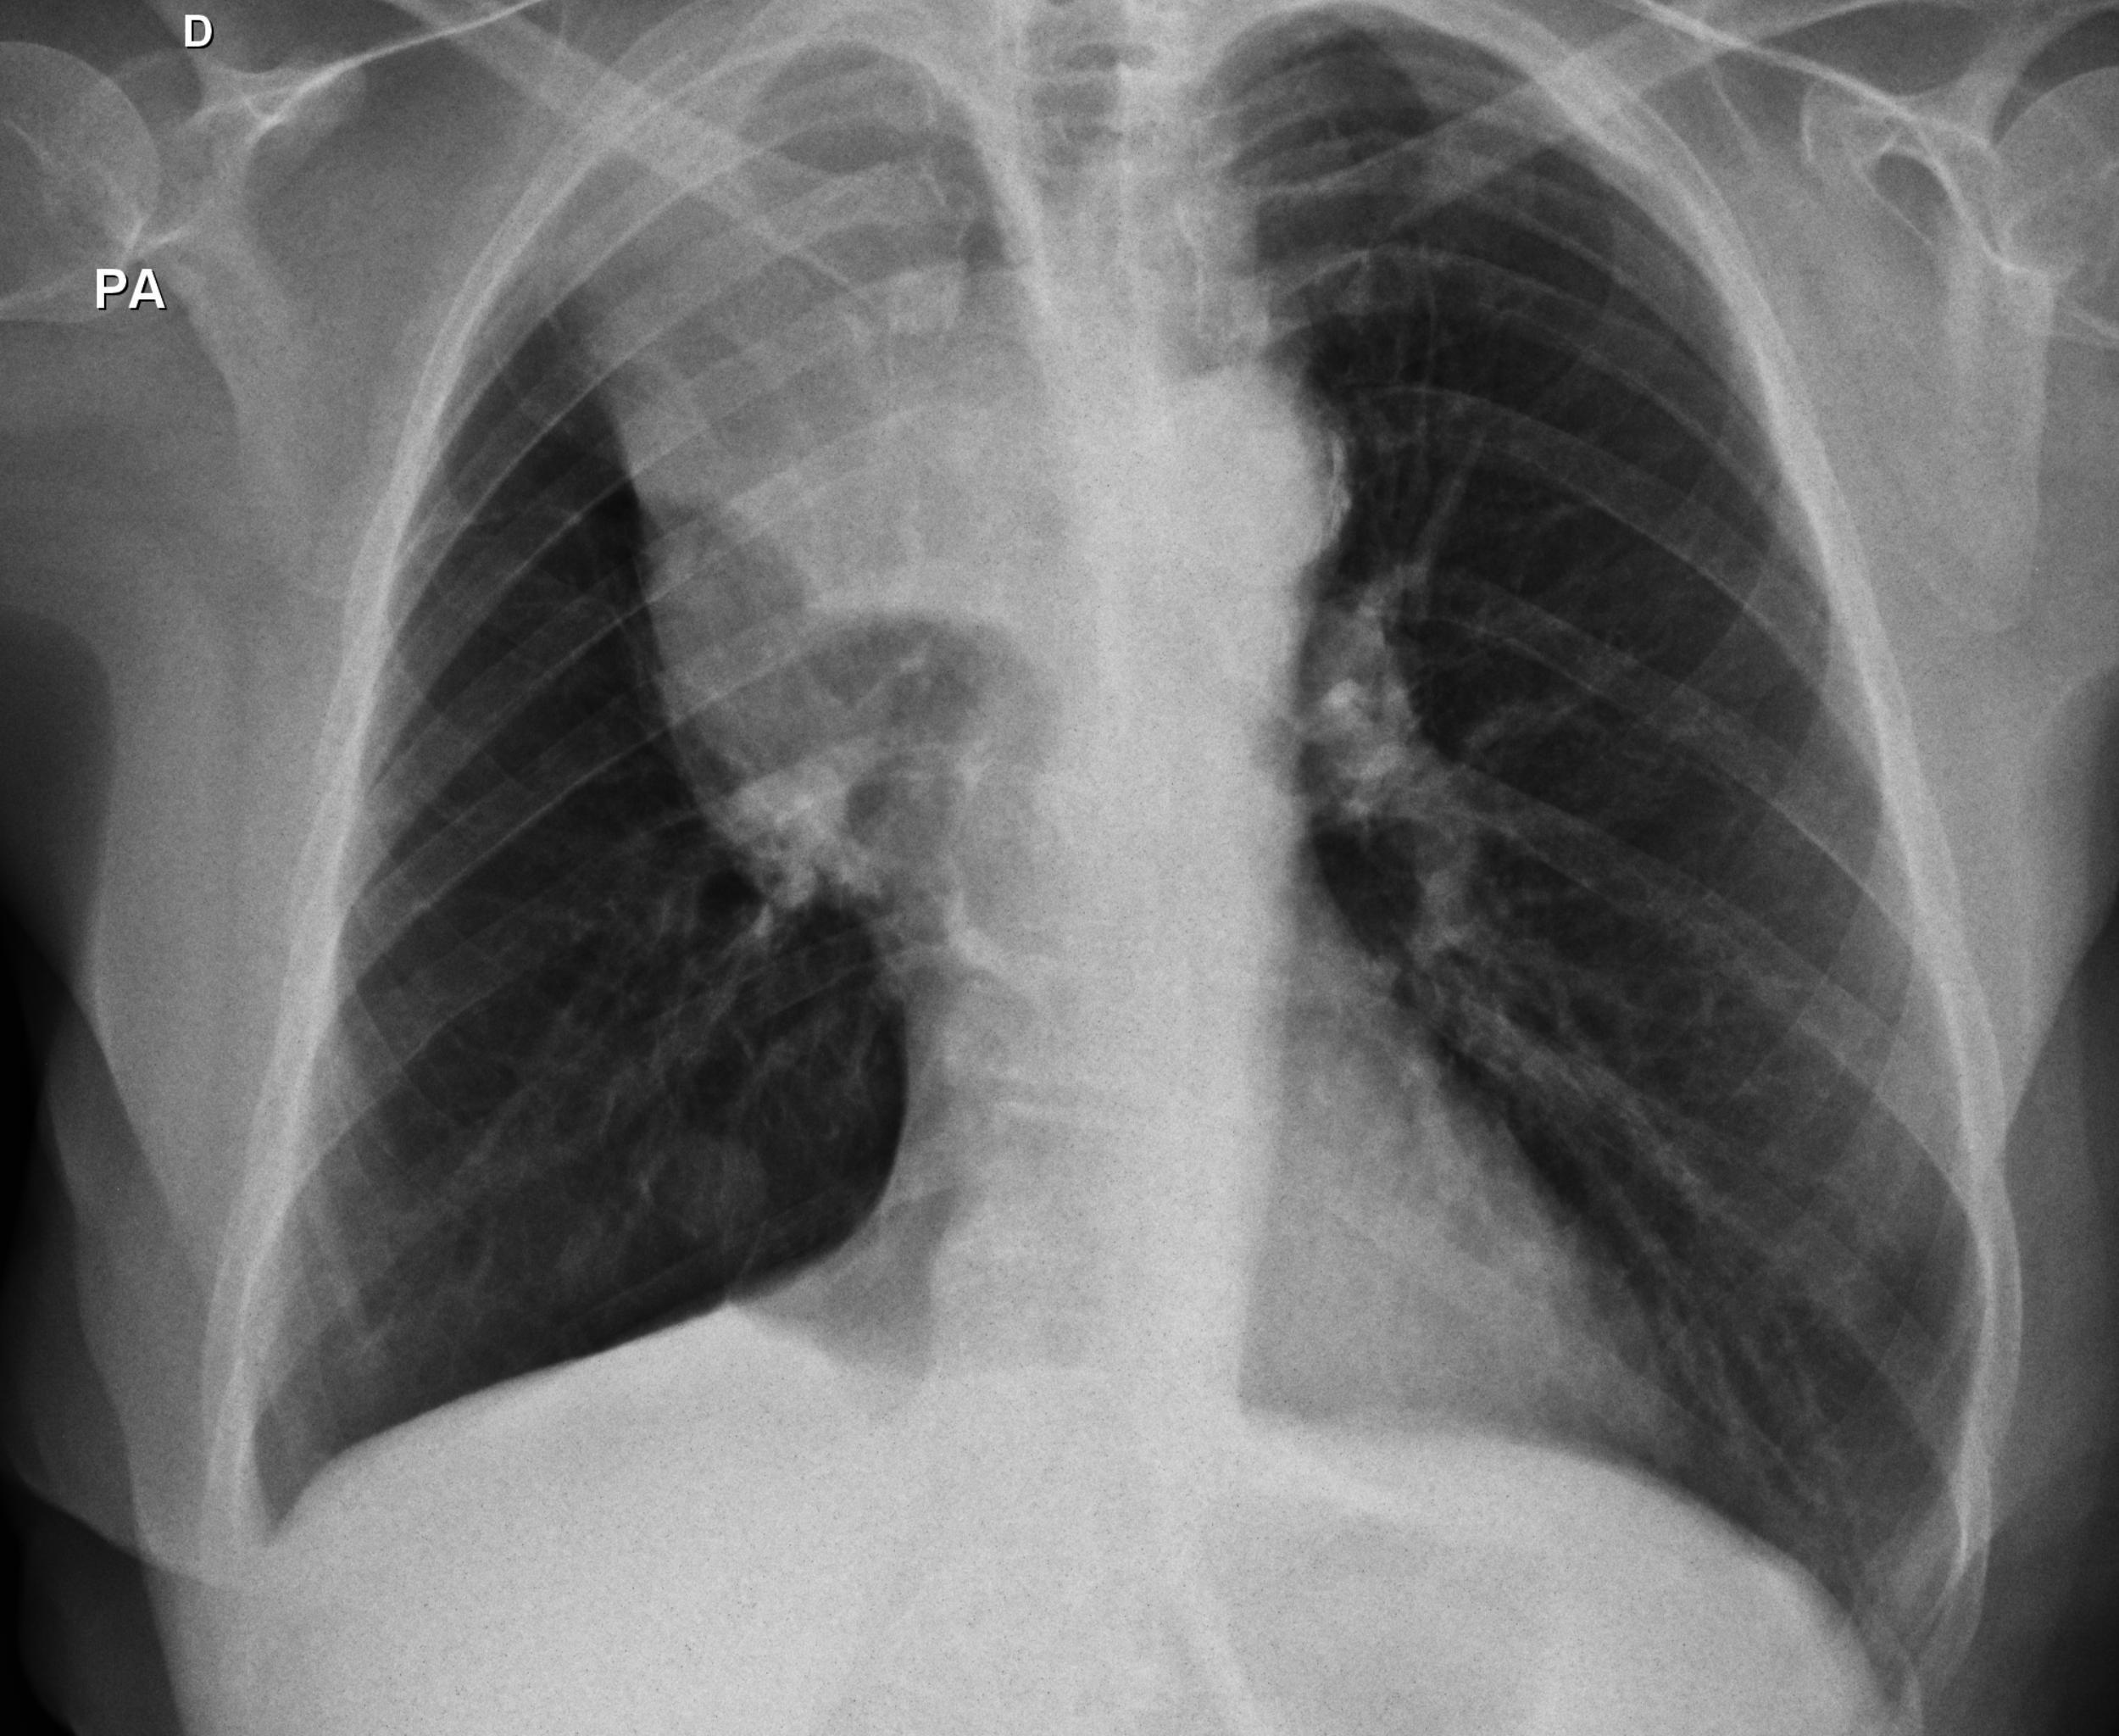

Caso relatado na Reunião de Discussão de Casos Clínicos do Hospital Universitário Prof. Polydoro Ernani de São Thiago, iniciada pelos Profs. Jorge Dias de Matos, Marisa Helena César Coral e Rosemeri Maurici da Silva, em julho de 2017. No dia 14 de junho de 2018, no auditório do HUPEST, realizou-se a apresentação e discussão do caso cujo registro é apresentado a seguir. Trata-se da discussão de onze casos em radiologia torácia, de forma interativa com a plateia, e assim ocorre também neste artigo.